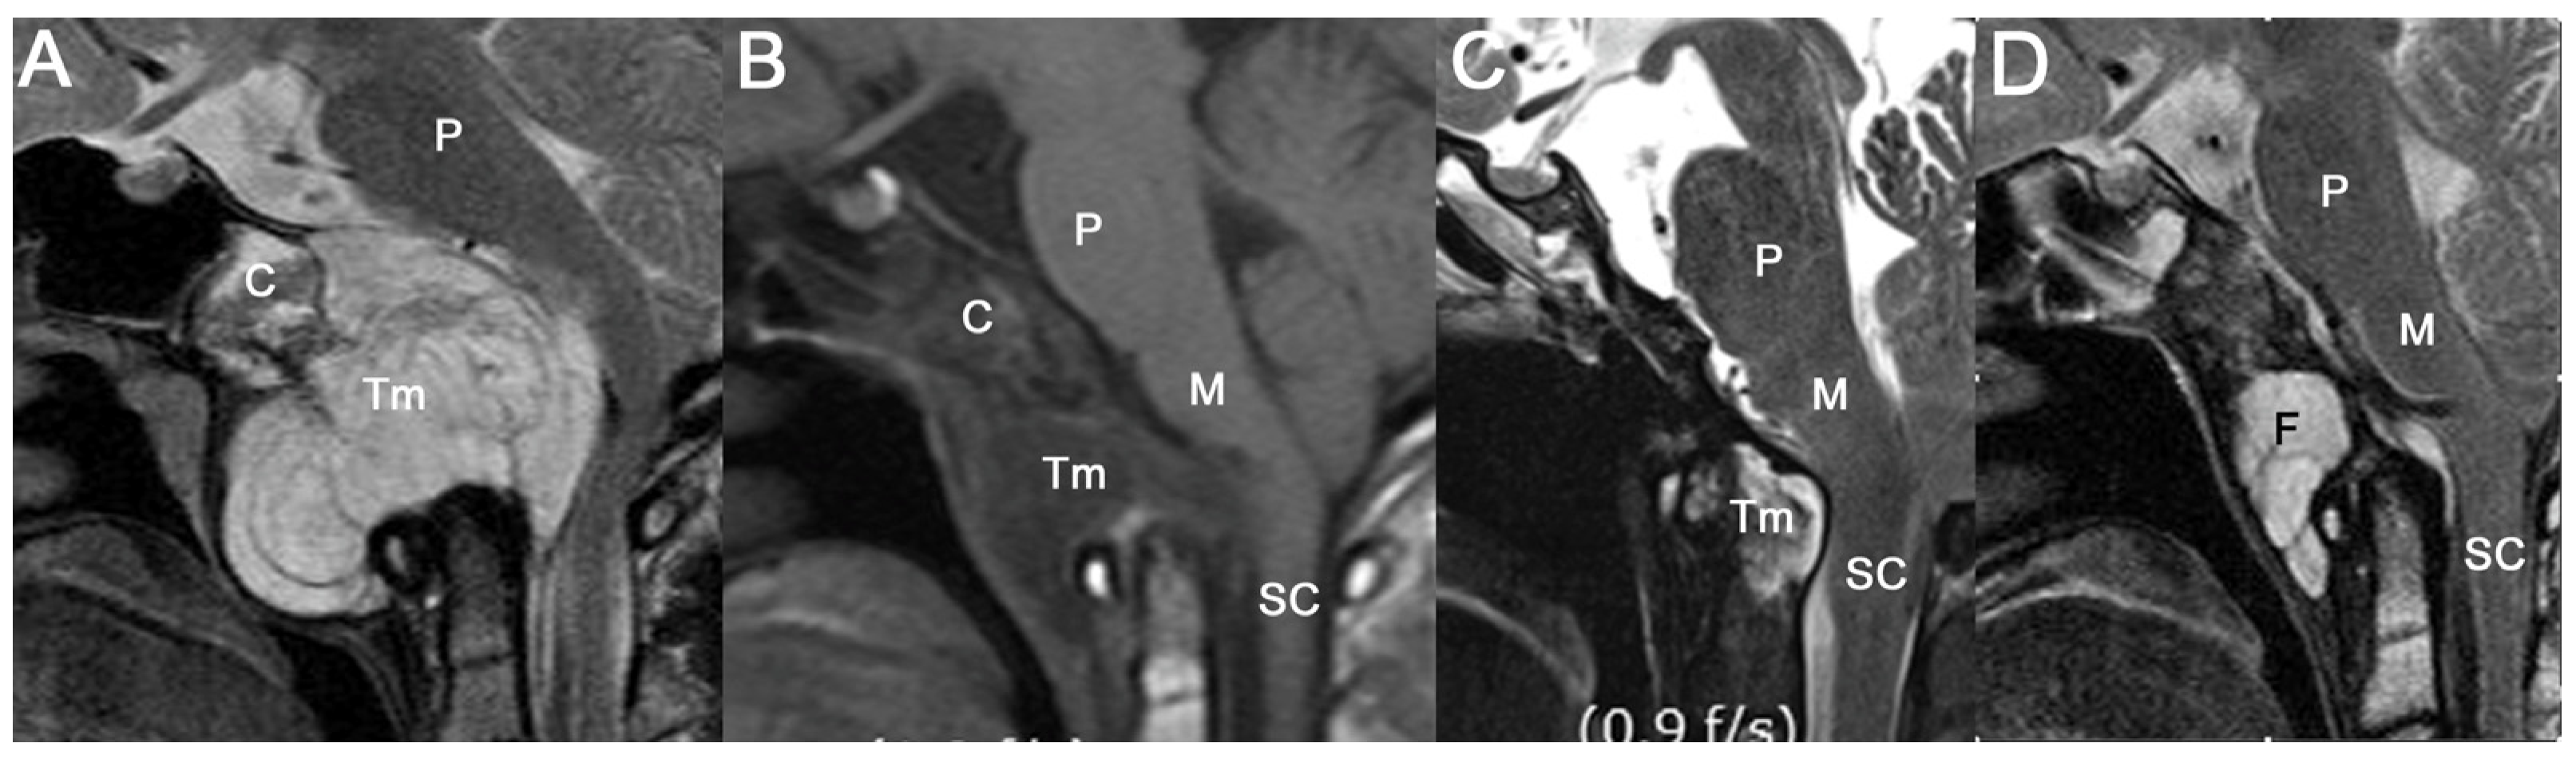

3.1. Tumor Locations and Invasion of Critical Structures

3.2. Overall Outcomes

3.3.3. Progression-Free Survival Based on a Remnant Brainstem Lesion